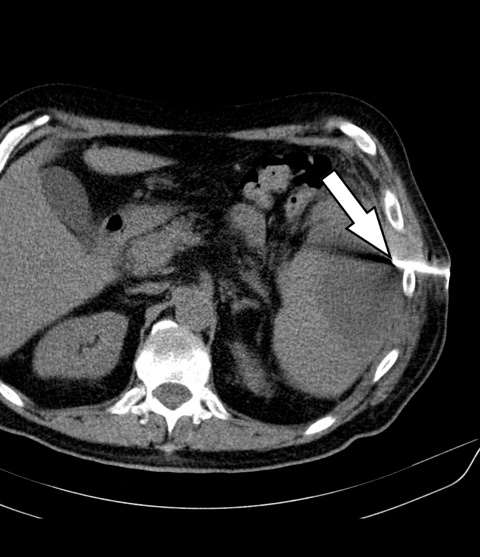

in Seldinger-Technik: Dargestellt ist die Kontrolle des intercostalen

Zugangsweges (Pfeil).

Im interdisziplinären Konsens erfolgte noch am selben Tag die interventionelle Therapie mittels CT-gestützter Drainageneinlage. In Rückenlage wurde nach Lokalanästhesie unter sterilen Kautelen in Seldinger-Technik CT-gesteuert ein 12F-Pigtailkatheter implantiert (Abbildung 2). Hierbei entleerten sich 240 ml einer eitrig-trüben übelriechenden Flüssigkeit. Proben zur mikrobiologischen Diagnostik wurden asserviert. In der abschließenden computertomografischen Lagekontrolle zeigte sich der Milzabszess vollständig entleert und kollabiert (Abbildung 3).